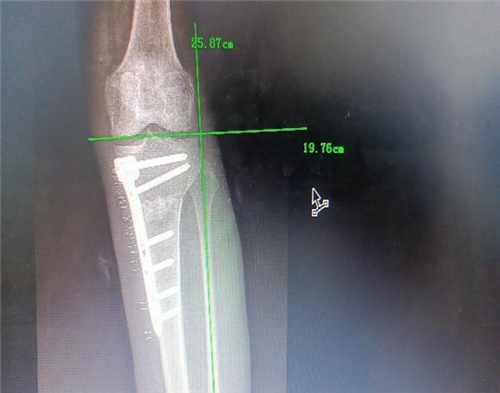

手术如期进行,在骨科手术机器人“透视眼”和“稳定手”的精准操作下,患者术中测量内翻畸形纠正,胫骨近端后倾角92°。术后,患者左膝疼痛明显缓解,关节活动度较术前明显改善,术后3天即扶拐下地行走,4周后即可完全负重。